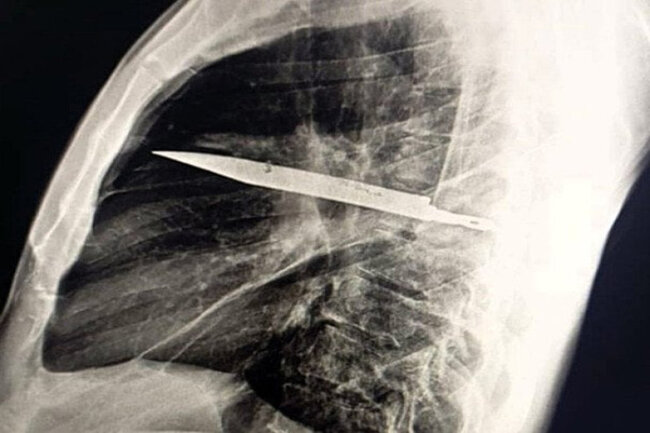

Sinə qəfəsinin rentgen müayinəsi qeyri-adi simptomların əsl səbəbini üzə çıxarıb — sinə boşluğunun ortasında böyük bir bıçaq tiyəsi ilişib qalıb. O, sağ kürək sümüyündən keçərək möcüzəvi şəkildə heç bir həyati vacib orqana toxunmayıb.

Əməliyyat zamanı cərrahlar ehtiyatla bıçağı çıxarıb, həmçinin ölmüş toxuma səbəbindən yaranmış irini təmizləyiblər. Pasiyent reanimasiya şöbəsinə köçürülüb və orada 24 saat qalıb, daha sonra ümumi palataya keçirilib. Orada isə həkim nəzarəti altında daha 10 gün müalicə alıb.